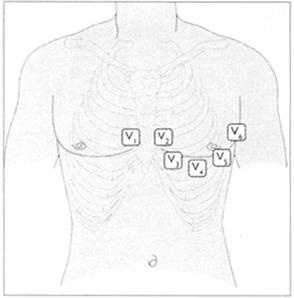

听诊器有两个主要功能即收纳从胸壁传导的声音而滤去外源性杂音以及对某特定频率的声音进行强化。一般说来,钟型听诊器用于听低频声音,而膜件用于听高频声音。在心尖区你可以使用两种听诊器,可以听到由二尖瓣狭窄引起的低频舒张期杂音和二尖瓣返流时出现的全收缩期杂音。然后再用膜件分别对图28所示的各听诊区进行听诊。各听诊区分别是胸骨左缘(三尖瓣听诊区)(图29),胸骨左缘第2肋间(肺动脉瓣听诊区)(图30),胸骨右缘第2肋间(主动脉瓣听诊区)(图31),左腋前线第5肋间(二尖瓣听诊区)。

●肢导一般是水平的,如果不是就用表13所示的彩色电极。最好把电极放在无汗毛的区域,如前臂的内侧和腿的外侧,踝关节之上电极放置的位置见表14和图40。

表14 胸导联的位置

图40 胸导联的位置